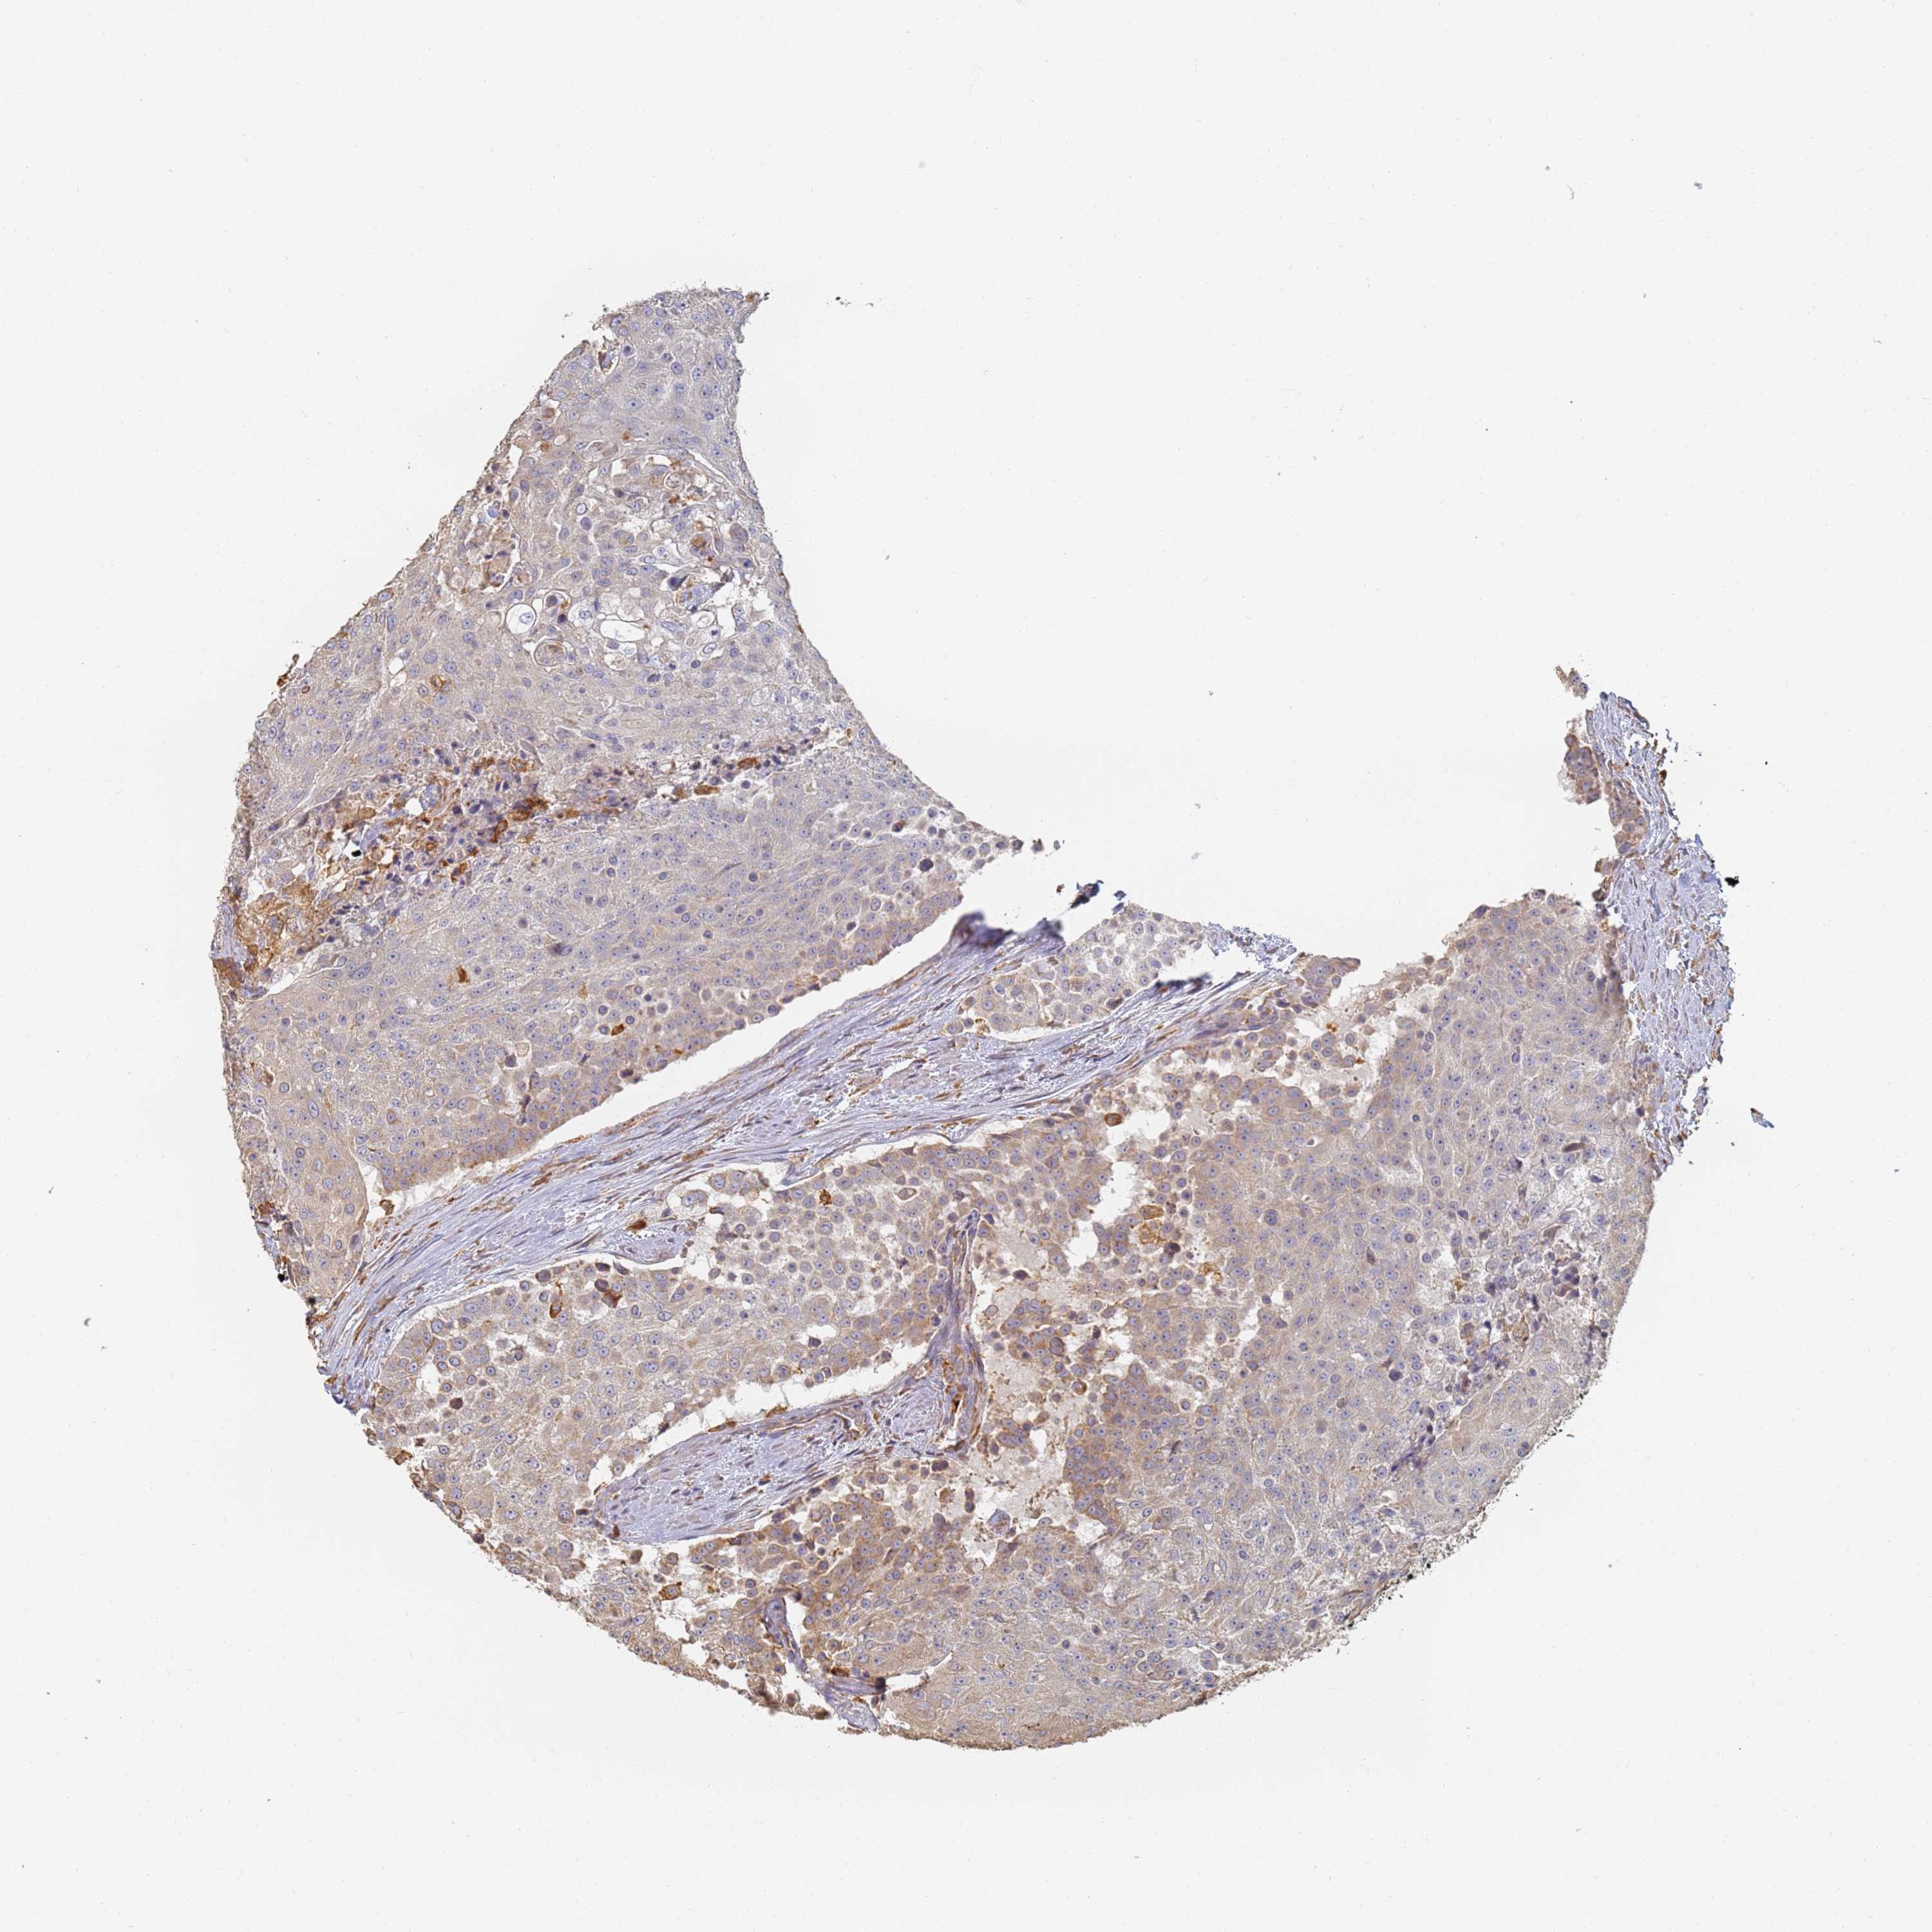

UROTHELIAL CANCER - Protein expressioni

A mouse-over function shows sample information and annotation data. Click on an image to view it in a full screen mode. Samples can be filtered based on level of antibody staining by selecting one or several of the following categories: high, medium, low and not detected. The assay and annotation is described here.

Note that samples used for immunohistochemistry by the Human Protein Atlas do not correspond to samples in the TCGA dataset.

Antibody stainingi

Antibody staining in the annotated cell types in the current human tissue is reported as not detected, low, medium, or high, based on conventional immunohistochemistry profiling in selected tissues. This score is based on the combination of the staining intensity and fraction of stained cells.

Each image is clickable and will lead to virtual microscopy that enables deeper exploration of all samples and also displays staining intensity scores, fraction scores and subcellular localization as well as patient and tissue information for each sample.

Antibody HPA038666

Antibody HPA038667

Urothelial carcinoma, High grade

Urothelial carcinoma, Low grade